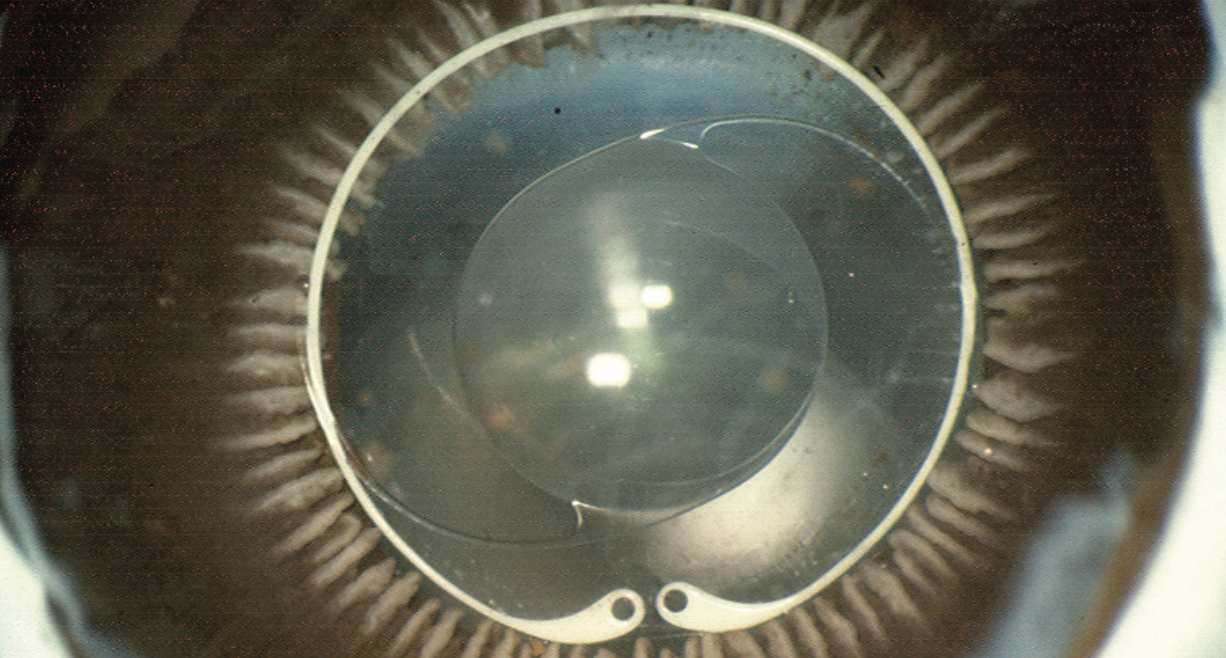

Ophtec’s capsular tension ring in use

Perfectly circular capsular bag. Ophtec tension rings are designed to be more flexible and not deform the capsular bag.